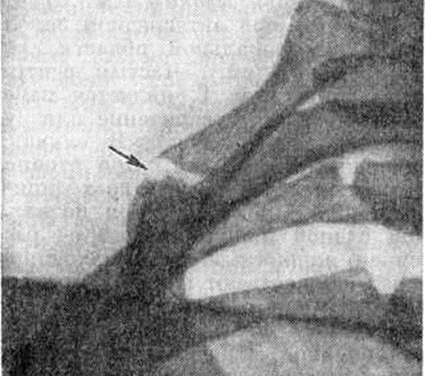

Рентгенография играет ключевую роль в диагностике синдрома Титце. С помощью рентгеновских снимков врачи могут отслеживать изменения в хрящевых тканях. Такие исследования следует проводить каждые 2–3 месяца. Кроме того, рентгенография позволяет исключить вероятность злокачественной опухоли.